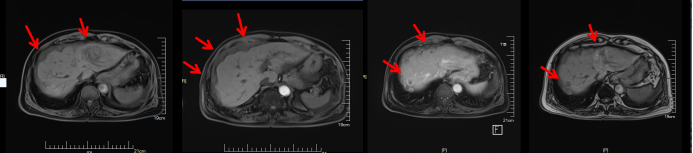

影像学评估:

图6、呋喹替尼单药治疗期间,影像学评估持续SD:第1排(2020-05)、第2排(2020-07)、第3排(2020-09)、第4排(2020-11)